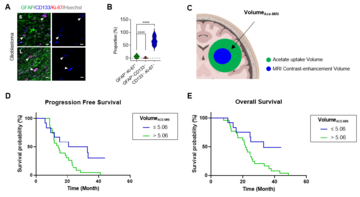

2024-01-16New Frontier in Glioblastoma Theragnosis - Visualizing Tumor Microenvironment

2024-01-16New Frontier in Glioblastoma Theragnosis - Visualizing Tumor Microenvironment